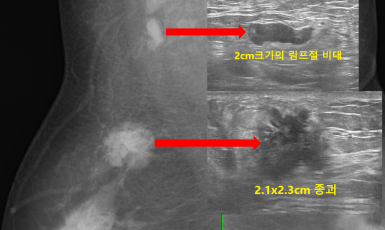

301번째 갑상선암 진단사례 (2019년4월8일) 갑상선과 관련된 특별한 증상없이 왼쪽 겨드랑이 통증을 주소로 내원해 주신 환자분이셨습니다. 유방 초음파상 ..

250번째 유방암 진단사례 (2019년4월9일) 한달전부터 왼쪽 유방에 갑작스럽게 단단한 멍울이 잡혀 검사위해 내원한 환자분이셨습니다. 진찰했을때 촉진해 보지 않아도 ..